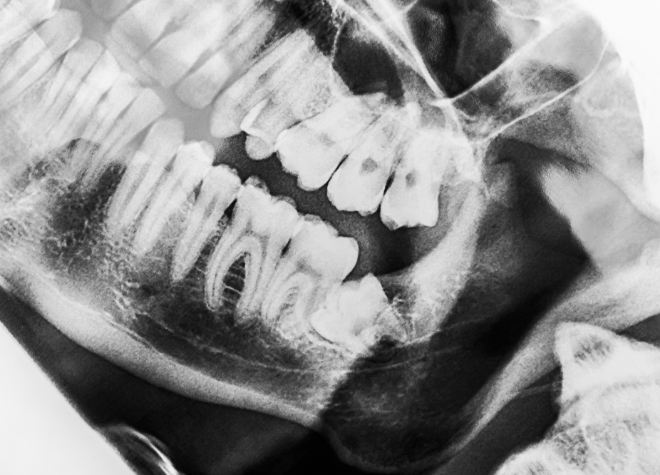

親知らずの抜歯をする際は、まずレントゲンや歯科用CTで入念に診査・診断を行います。その結果をもとに、当院で対応することが難しい場合には、大学病院を紹介させていただくこともあります。